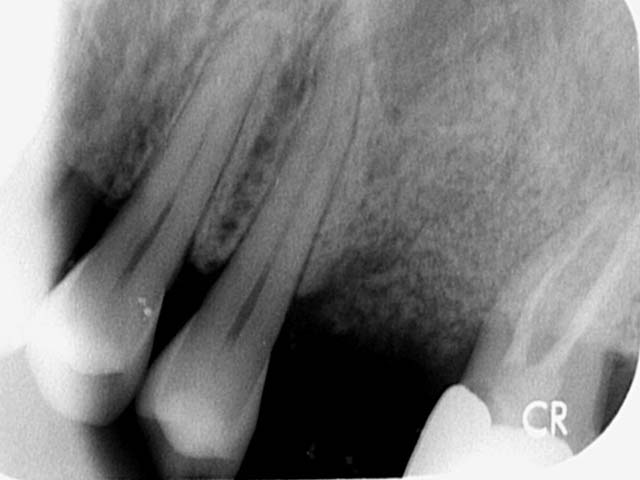

微創植牙 首頁 案例分享 人工植牙 微創植牙 微創植牙 牙周病的牙齒,因為骨頭破壞,只好拔除 拔牙後,置入骨粉,靜待骨頭癒合 晴美牙醫擁有豐富竹北微創植牙經驗,欲瞭解更多相關知識,可至診療項目-微創植牙頁面。 傷口癒合良好 微創不翻瓣 置入植牙 裝置假牙